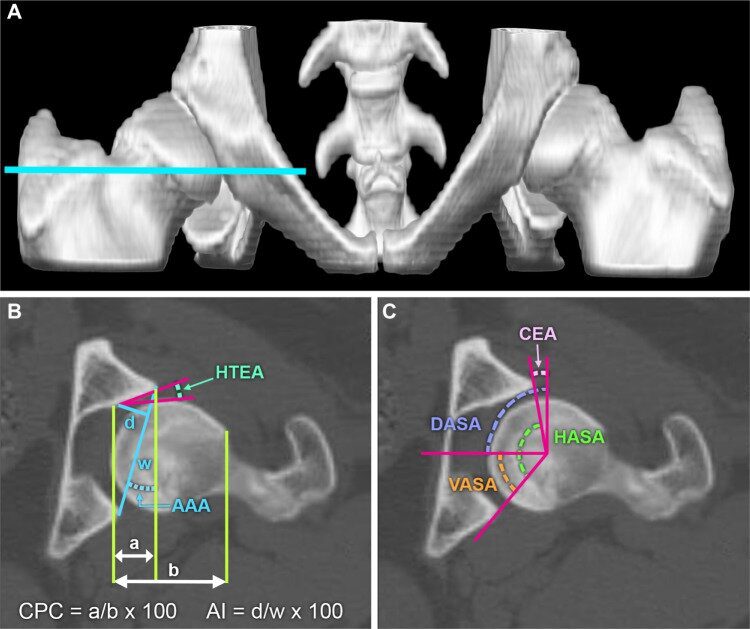

It uses three radiographic views and calculates a Distraction Index (DI), an objective numerical measurement of how loose or tight the hip joint is.

Orthopedic Foundation for Animals (OFA) evaluates hip conformation using a single extended-leg radiographic view. Radiologists visually assess the structure and assign a grade: Excellent, Good, Fair, Borderline, Mild, Moderate, or Severe.